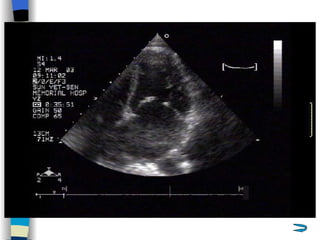

Echocardiography The most valuable technique for diagnosing MS, and determining its severity M-mode echo : Thickened, calcified leaflets open poorly, close slowly (EF slope ↓ ) The double peaks disappear Both leaflets move anteriorly during early diastole Two-dimensional echo: Fusion, thickening,  doming  of the valve leaflets, and poor leaflet separation in diastole;  mitral orifice area ↓

Doppler echo : Most accurate noninvasive technique for quantifying the severity of MS Spectrum Doppler: measure transvalvular gradient, MVA Color Doppler: display  high velocity color jet Provide other important information Cardiac chamber size (LA, RV) Left ventricular contractility Pulmonary arterial pressure Other coexisted valvular or congenital abnormalities  Mural thrombi